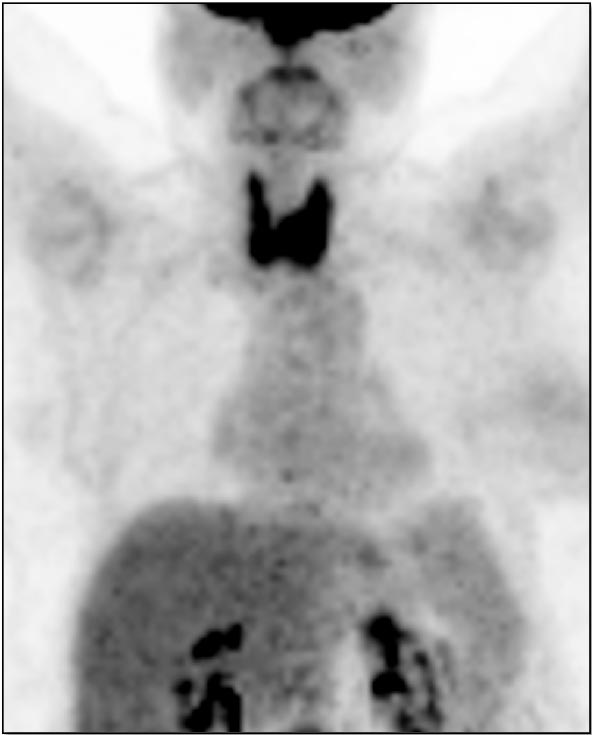

Diffuse Thyroid Uptake:

- The normal thyroid gland typically demonstrates little or no FDG uptake.

- Mild diffuse thyroid uptake is considered normal.

- Moderate to intense diffuse thyroid uptake can be normal, or can reflect thyroiditis. In such cases, we typically report, “Diffuse intense thyroid uptake is noted, which can reflect thyroiditis.”

Incidental Focal Thyroid Uptake:

- An incidental focus of thyroid uptake is seen in up to 4% of scans.

- Up to 33% of FDG-avid thyroid nodules will represent a primary thyroid malignancy (the nodule itself may be difficult to visualize on the non-contrast co-registered CT images).

- Therefore, any focus of uptake above background metabolic activity warrants further clinical assessment, typically ultrasound and biopsy.

Caveat:

- Beware the intensely avid thyroid nodule partially masked by diffuse intense thyroid uptake. While the diffuse uptake may be normal or may reflect thyroiditis, the underlying hot nodule may represent an incidental primary thyroid cancer.

- Parathyroid adenomas can also be hypermetabolic (we do not report this in our differential unless there is a high clinical suspicion for a parathyroid adenoma).